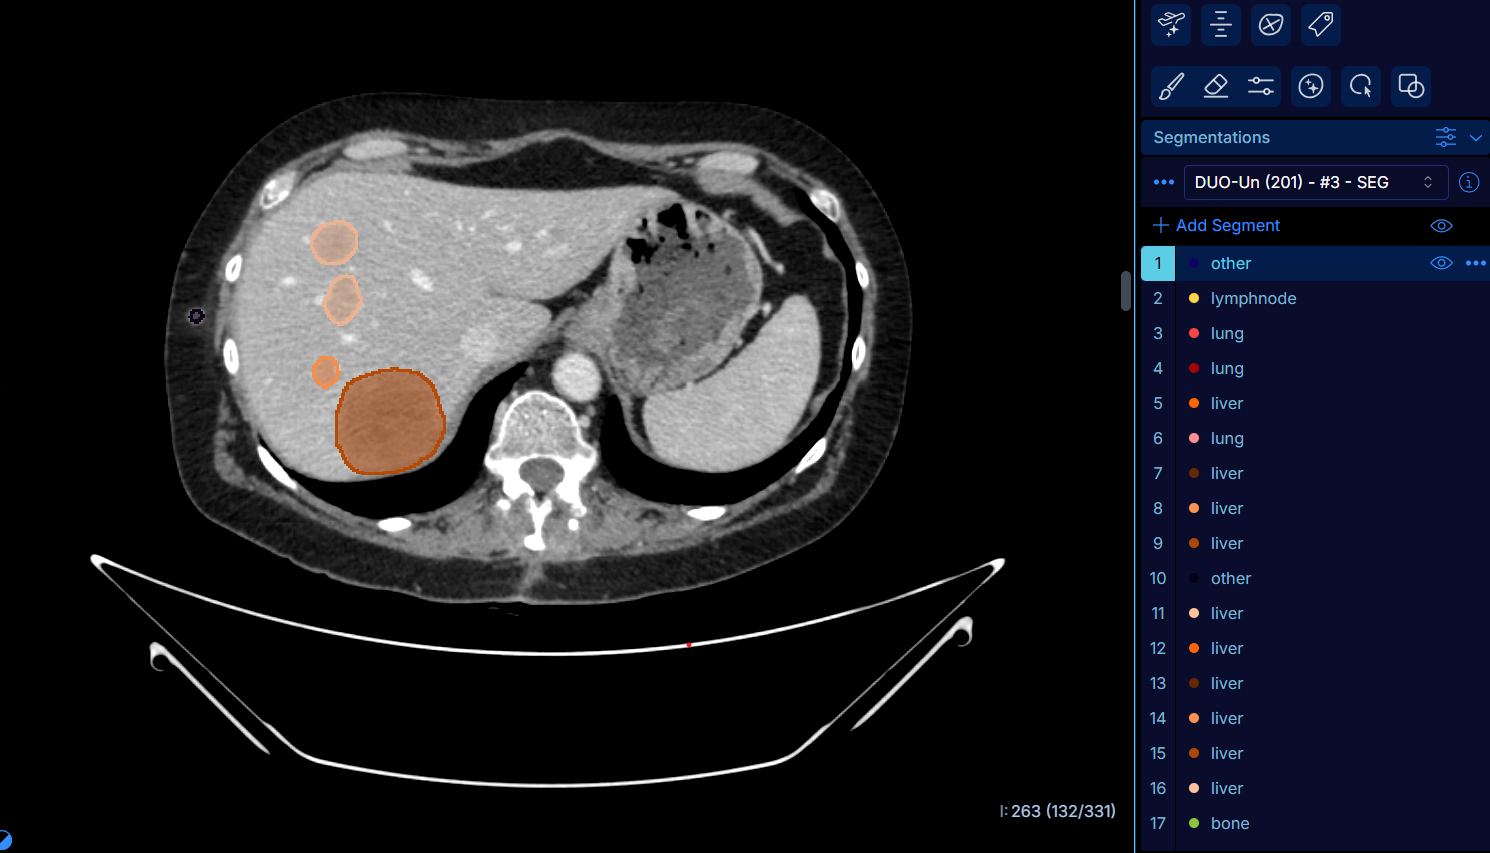

Un nouvel outil d’IA au service d’une détection optimale du cancer par imagerie

- Gustave Roussy,Gustave Roussy, dans le cadre d’un consortium réunissant Guerbet, Intrasense et le CHU d’Angers, a participé au développement d’un outil d’intelligence artificielle capable d’identifier automatiquement, à partir d’un scanner thoraco-abdomino-pelvien, les lésions cancéreuses présentes dans cette zone...